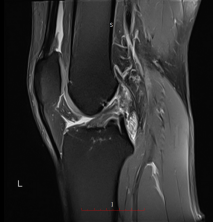

26岁的梁先生(化名)正值青春年华,却因关节损伤饱受折磨,经诊断为左膝前叉撕裂、半月板裂伤伴创伤性滑膜炎;53岁的邓先生(化名)则在日常活动中遭遇类似损伤,右膝同样出现前叉撕裂、半月板裂伤及创伤性滑膜炎的症状。

而他们还都有着共同的治疗期望——“最小损伤、最快恢复”的核心诉求,于是骨一区吴建伟主任团队结合两人的病情特点,迅速制定了适配的微创治疗方案。手术均采用“关节镜下膝关节探查清理+半月板修复+取同侧腓骨长肌重建前交叉韧带术”。

仅通过数个5-10毫米的微小切口,借助关节镜的高清视野精准操作,既彻底清理了病变组织、修复了损伤的半月板,又成功重建了前交叉韧带,实现了对关节功能的精准修复。这种微创手术方式不仅创伤小、出血少、术后疼痛轻,更能有效缩短恢复周期,让患者在更短时间内摆脱病痛,回归正常生活与工作。